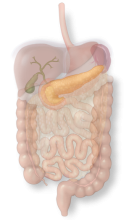

The gallbladder concentrates and stores bile as a pear-shaped sac which it can release to help digestion after a fatty meal.

The gallbladder concentrates and stores bile as a pear-shaped sac which it can release to help digestion after a fatty meal.

The duodenum is a C-shaped tube that receives food from the stomach and prepares it for chemical digestion further along in the intestines.

The omentum is a fatty apron that serves a protective role and helps filter immune responses to gut bacteria.

The colon is a large tube that stores feces and also contains helpful bacteria that breaks down food that has not yet been absorbed.

The stomach is a muscular sac that is important for absorbing food and preparing food for further digestion.

The liver is a solid organ that produces bile for fat digestion and is also the first stop for the majority of absorbed nutrients.

The pancreas is a gland that produces chemicals for food break-down as well as a hormone system that regulates sugar.